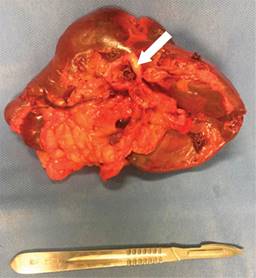

Femenino de 41 años, con antecedente de hipotiroidismo diagnosticado a los 21 años, actualmente sin tratamiento médico desde los 40 años por aparente control, diagnóstico de miomatosis uterina a los 40 años, sin tratamiento; antecedente de dos cesáreas, última a los 23 años, sin complicaciones. Accidente automovilístico con volcadura a los 40 años, sin daño orgánico aparente. Inicia padecimiento actual posterior a accidente automovilístico ocurrido un año previo con dolor en hipocondrio izquierdo, de tipo intermitente, punzante, sin irradiaciones, sin agravantes ni atenuantes; a la exploración física presenta dolor en hipocondrio izquierdo a la palpación profunda, resto sin datos patológicos. Se realizó ultrasonido con hallazgos compatibles con aneurisma de la arteria esplénica y colelitiasis, se complementa abordaje diagnóstico con angiotomografía de aorta abdominal encontrando arteria esplénica de calibre normal, con dilatación focal sacular en segmento distal compatible con aneurisma de 17.7 × 15.9 mm y cuello de 5.5 mm, con trombo mural de 2 mm, sin signos de ruptura, litiasis vesicular y miomatosis uterina. En manejo conjunto con angiología se realiza embolización selectiva con colocación de coils, sin complicaciones aparentes (Figura 1). En el seguimiento inmediato, la paciente presenta dolor abdominal y leucocitosis, se realiza nueva angiotomografía con datos sugestivos de oclusión de arteria esplénica e infarto esplénico (Figura 2). Por los hallazgos comentados se decide realizar esplenectomía y colecistectomía convencional mediante abordaje quirúrgico con incisión en línea media, supraumbilical, con los siguientes hallazgos: vesícula biliar de paredes delgadas, múltiples litos en su interior de 5-10 mm aproximadamente, arteria cística de 2 mm, conducto cístico de 3 mm, bazo de 13 × 10 cm aproximadamente, con múltiples zonas isquémicas, aneurisma de la arteria esplénica a nivel de hilio esplénico, posterior a su bifurcación (Figura 3). Cursa el postoperatorio sin complicaciones, por lo que fue egresada tres días después de la cirugía, recibió vacunación correspondiente para pacientes esplenectomizados. Reporte histopatológico con hallazgos de aneurisma de arteria esplénica con ateroesclerosis, parénquima esplénico con vasos congestivos y colecistitis crónica litiásica.

Figura 2: Angiotomografía abdominal. A) En corte coronal se identifica material de densidad metálica correspondiente a coils localizados en segmento distal de arteria esplénica previos a hilio esplénico. B) Se observa opacificación y captación del contraste a nivel esplénico de forma irregular heterogénea tanto en la fase arterial como venosa, apreciando una zona extensa que involucra a la mayor parte del parénquima esplénico desde el hilio, sólo respetando el polo superior y el inferior compatible con infarto.